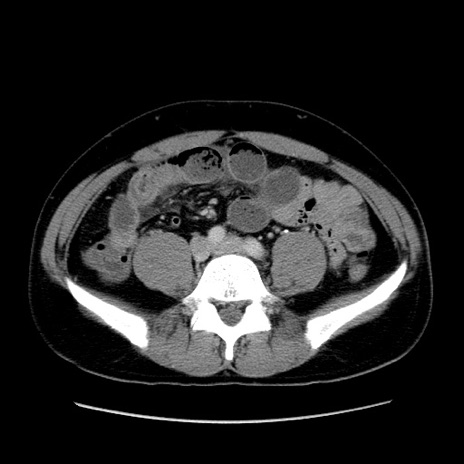

冠状断像

【症例】30歳代男性

【主訴】腹痛、嘔吐

【現病歴】昨晩から突然の腹痛あり、その後嘔吐、軟便も出現。腹痛が改善しないため救急搬送となる。2日前にしめ鯖の食事歴あり。

【身体所見】意識清明、苦悶様、BP 135/90mmHg、BT 35.7℃、腹部:平坦、やや硬、心窩部〜臍部に自発痛、圧痛あり、筋性防御+、反跳痛-

【データ】WBC 8100、CRP 0.57